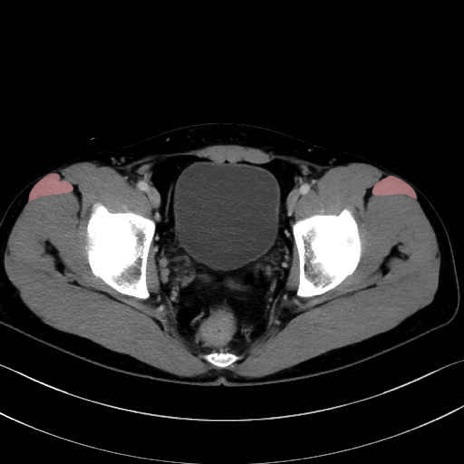

大腿筋膜張筋 (Tensor fasciae latae)